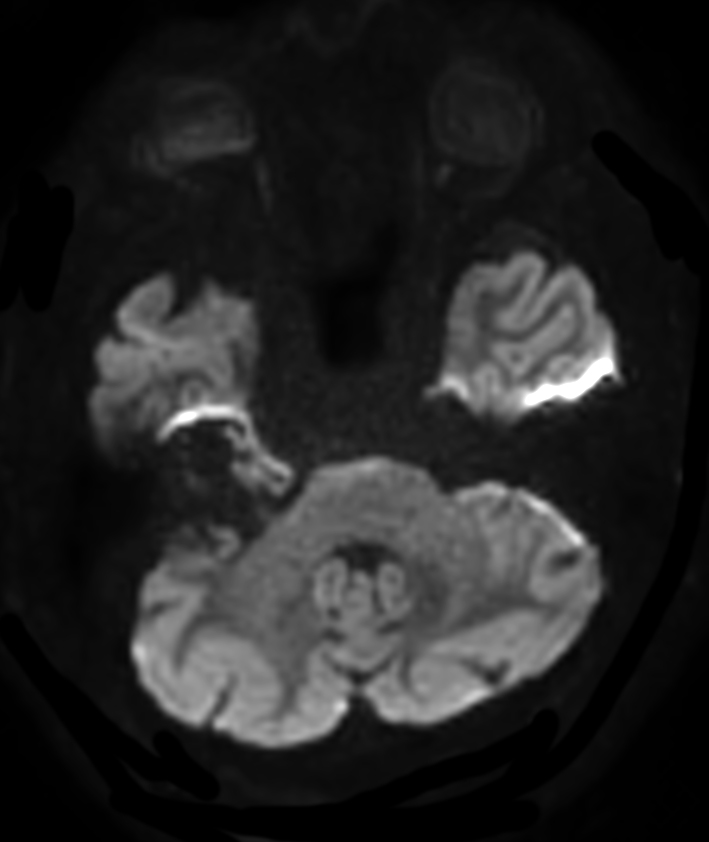

Patient with an IAC lesion. Comparing different DWI methods (EPI, TSE, ZOOM). Compressed SENSE is added to all TSE sequences to decrease scan times, thereby shortening the time the patient has to spent in the magnet. The dS Head 32ch coil is used to enhance image quality.

DWI EPI (b1000)

DWI EPI high res (b1000)

DWI EPI ZOOM (b1000)